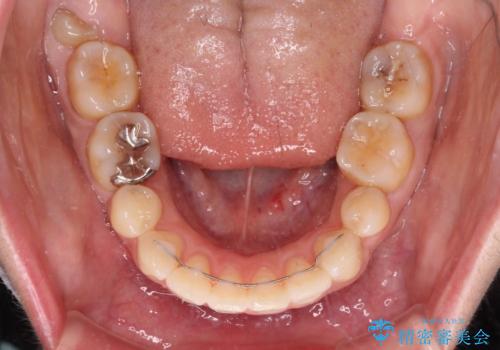

積極的に前歯を牽引したことで、口元の閉じにくさは顕著に改善され、横顔のシルエットが大幅に変化しました。

- 2年10ヶ月

- 10-30回